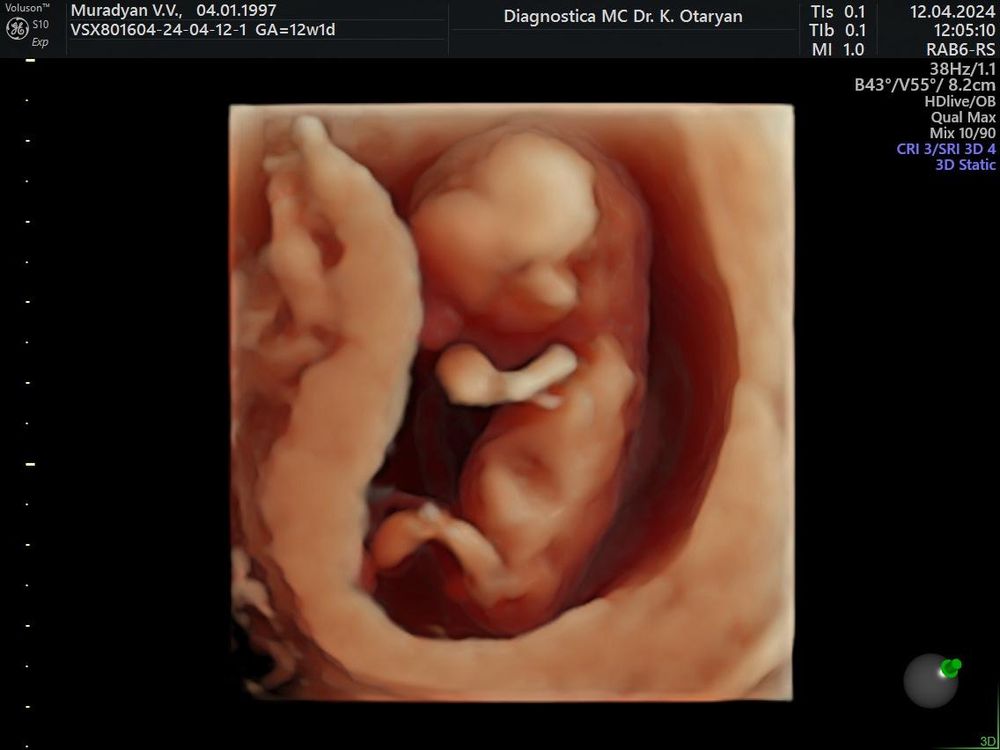

12 недель 1 день, первый скрининг❣️12.04

По развитию опережаем на 5 дней

ЧСС 161 уд/мин

КТР 64 мм

Врач сказала, все отлично развивается, смотрела час, первый скрининг прошли на пятерку)

сказали 95% мальчик, но кто бы ни был, очень ждём и любим 🩶🩶🩶